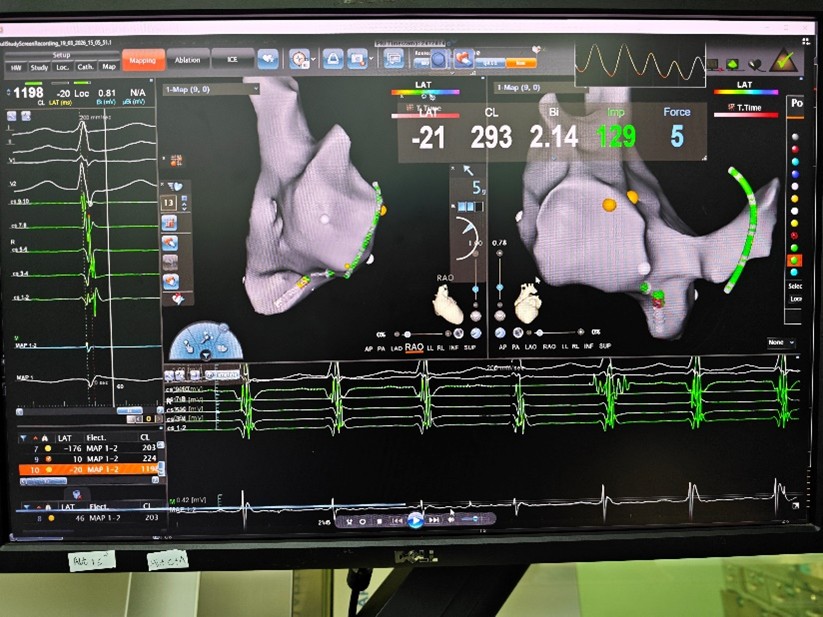

手术中,张志辉教授与罗文治主治医生凭借丰富的血管穿刺经验,精准建立手术路径。借助先进的三维电解剖标测平台,他们实时监测导管走形与头端压力,将导管顺利送入心腔。在心腔内,无需X射线辅助,团队迅速建立三维心腔模型,精准锁定并成功消融引发心动过速的异常病灶。整台手术历时不到一小时顺利收官,全程无放射线暴露,心律失常得以根治,胎儿安全也得到了最大程度的保障。

图一:三维心腔图

图二:成功消融病灶